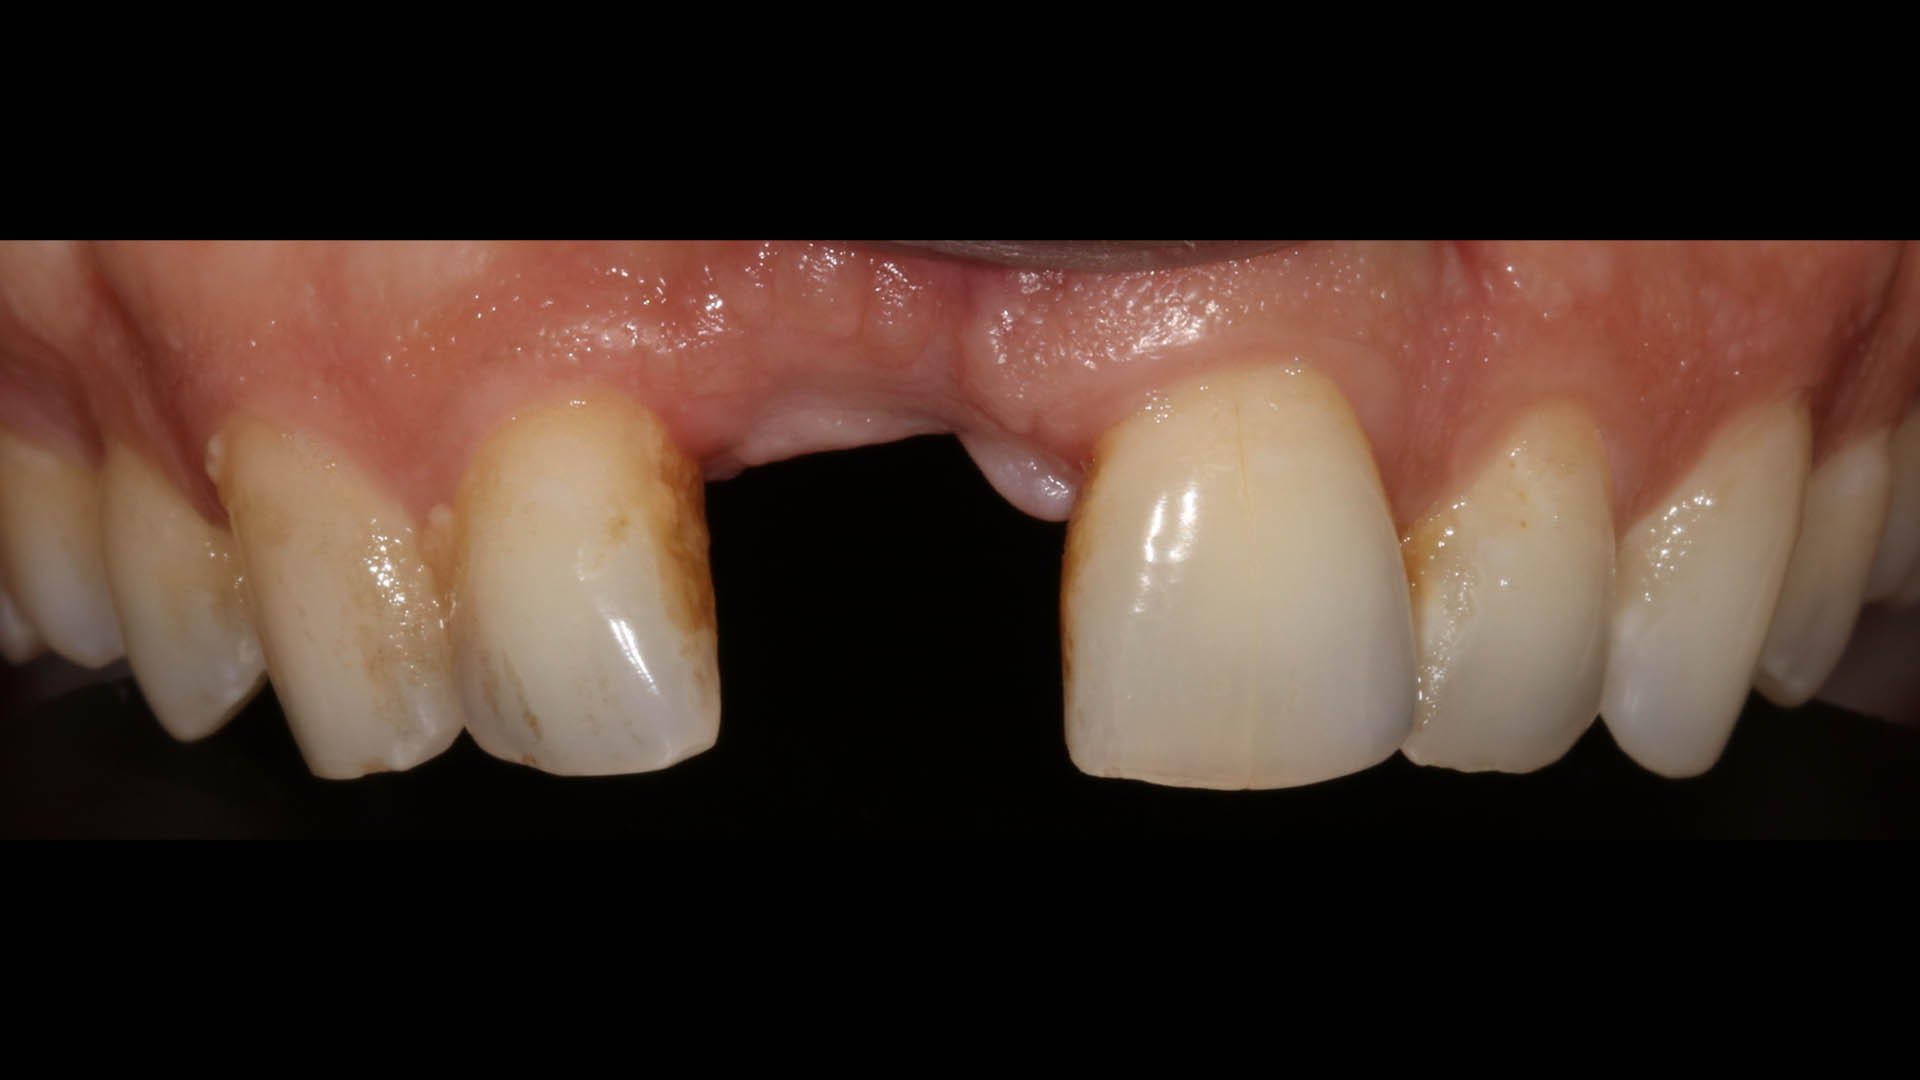

Take a glimpse into the magic of Coral Gables Dentistry through our before and after pictures. See firsthand the incredible smile makeover transformations that have brought confidence and joy to our patients.